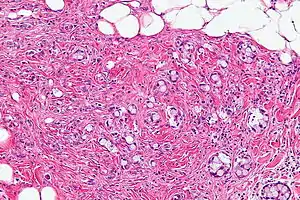

Micrograph of a goblet cell carcinoid. H&E stain.

GCCs are diagnosed by pathology. They have a characteristic biphasic appearance which includes (1) goblet cell-like cells, and (2) neuroendocrine-type nuclear chromatin (stippled chromatin).